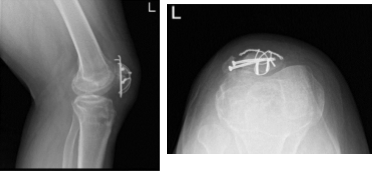

The fracture was reduced back and held with clamps. The two K-wires were passed. C-arm was introduced and checked and found to be acceptable reduction; 2 cannulated cancellous screws were inserted for fixation and compression.

Left Knee X-ray Complete with Patella

Patient checked in for a follow up visit after a month and saw significant improvement on his knee. Results for the X-ray were presented and showed revision of the fractured patella with no instrumentations.

Since prior examination noted the presence of a 1.4 cm cystic lesion in the anterior aspect of the medial patella, dislocation has been developed since prior examination.